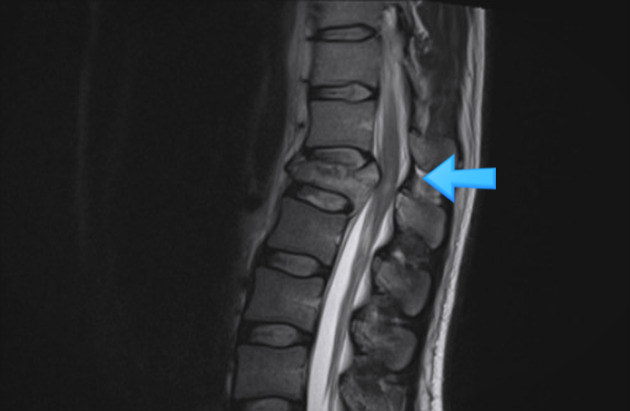

압박골절로 인해 척수 신경이 눌린다면 하지 저림, 마비, 배변 장애 등의 증상이 나타날 수 있습니다. 이런 경우는 추가적인 척수 신경 손상을 막기 위해 여러 개의 척추를 금속으로 고정하는척추 유합술 치료가 필요합니다.